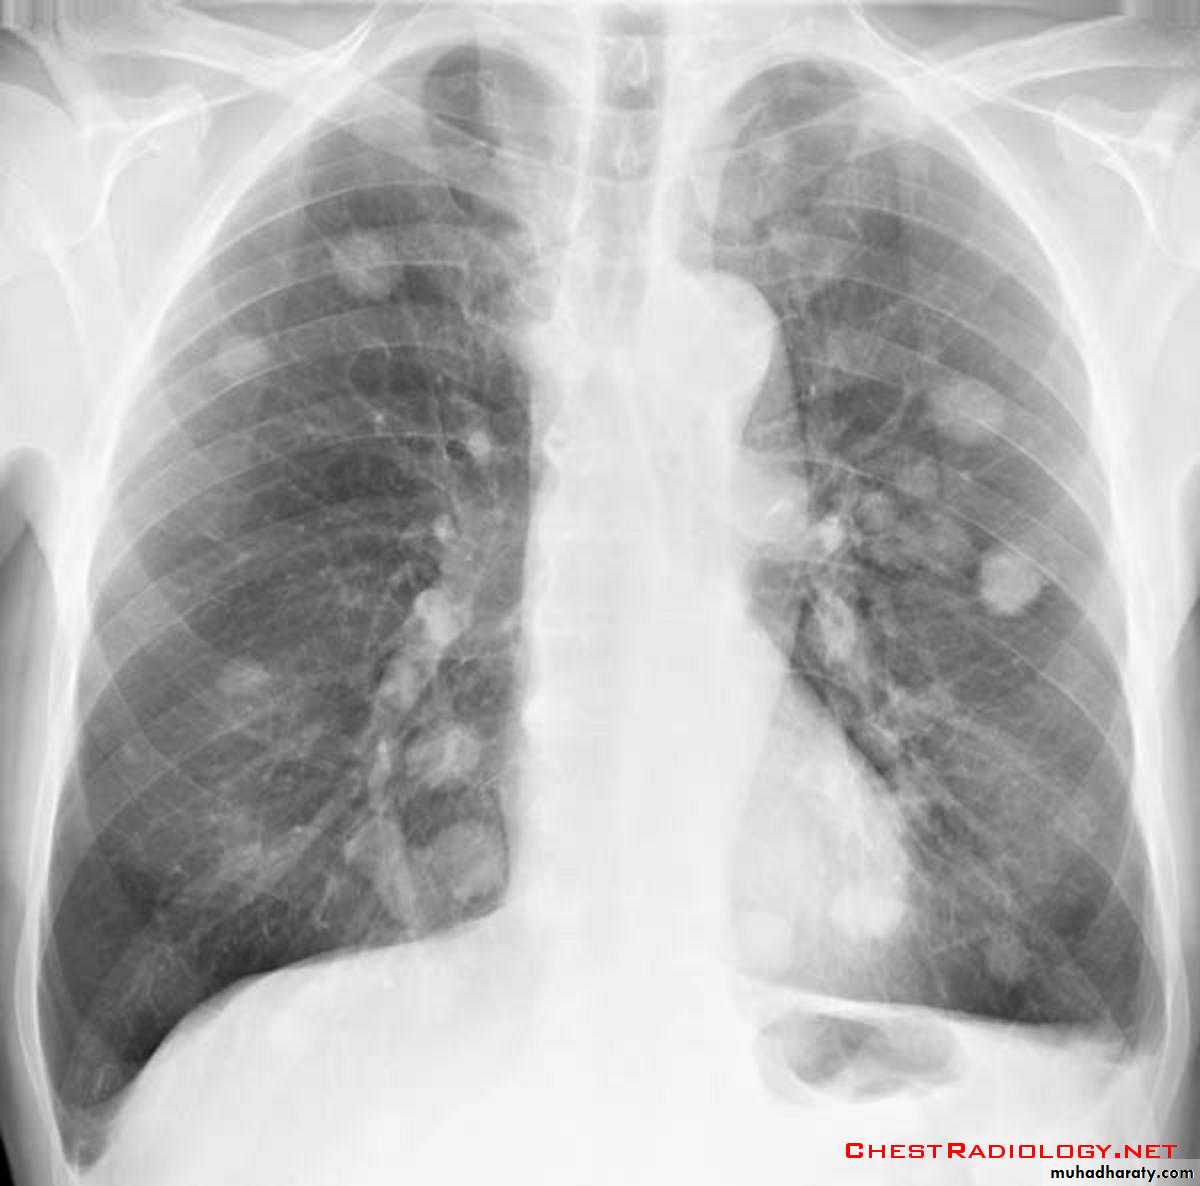

Pulmonary metastases are common and the result of metastatic spread to the lungs from a variety of tumors and can spread via blood or lymphatics.1.Cannonball metastases refer to large well circumscribed, round multiple opacities like cannonballs